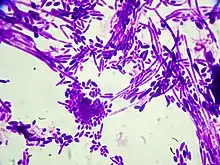

| Coloração de Gram de células Candida dubliniensis (ampliado de 1000 vezes) | |